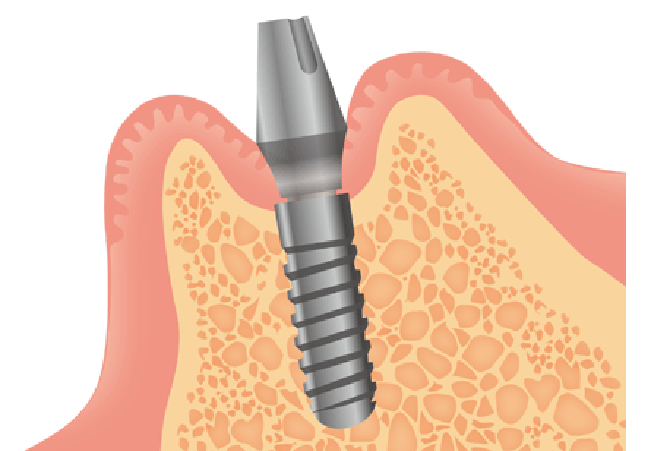

STEP4 インプラント手術(必要に応じて骨の再生を行う)

インプラントを入れるタイミングがきたらインプラントを入れる手術を行います。しかし顎の骨が細すぎたり低すぎたりするとインプラントを埋められません。そのような時は骨のボリュームを増やすために、骨の移植を行うことがあります。下あごの奥のほうから骨をとったり、人工的な材料を使って骨を増やします。

手術に関しては麻酔をして歯茎を切開して顎の骨に穴を開けていきます。その後顎の骨にインプラントを埋めます。インプラントがしっかり埋まっていることを確かめてから歯茎を戻して縫い合わせます。この時にインプラントの頭の部分を口の中に出す方法と、頭を全て歯肉で覆ってしまう方法があります。

STEP5 骨とインプラントが結合するのを待つ

人工歯根と顎の骨が結合するまで、約6週間〜24週間待機します。待機期間中はインプラントに仮歯を装着するか、インプラントを一度完全に歯茎の中に埋めるか骨の状態によって変わっていきます。